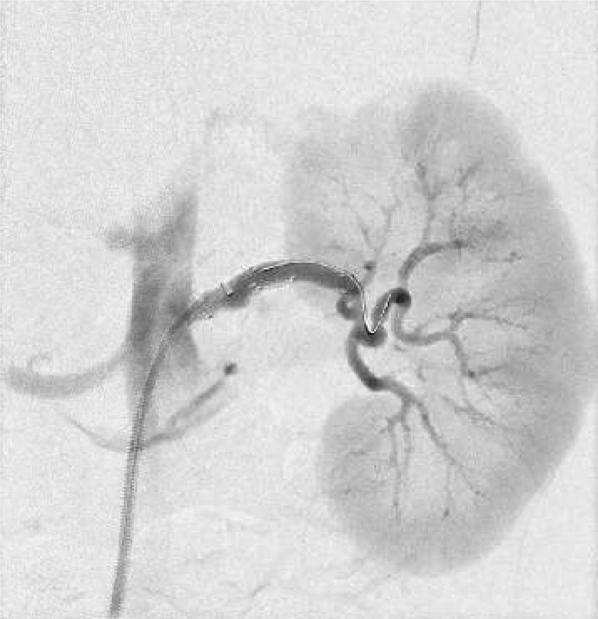

Leber hereditary optic neuropathy is an inherited, rare, mitochondrial metabolic disease that leads to progressive vision loss due to the accumulation of reactive oxygen species. The disorder has been associated with microangiopathy and macroangiopathy. We present a novel case of saccular left renal artery aneurysm in a 27-year-old man with known Leber hereditary optic neuropathy. The lesion was asymptomatic and grew from 1.8 to 2.0 cm during the course of 1 year. We successfully performed an endovascular left renal artery aneurysm repair.

Leber遗传性视神经病变是一种遗传性、罕见的线粒体代谢疾病,由于活性氧的积累导致进行性视力丧失。该疾病与微血管病变和大血管病变有关。我们报告了一例27岁患有Leber遗传性视神经病变男性的左肾动脉囊状动脉瘤新病例。该病变无症状,在1年的病程中从1.8厘米增大至2.0厘米。我们成功实施了左肾动脉动脉瘤血管内修复术。